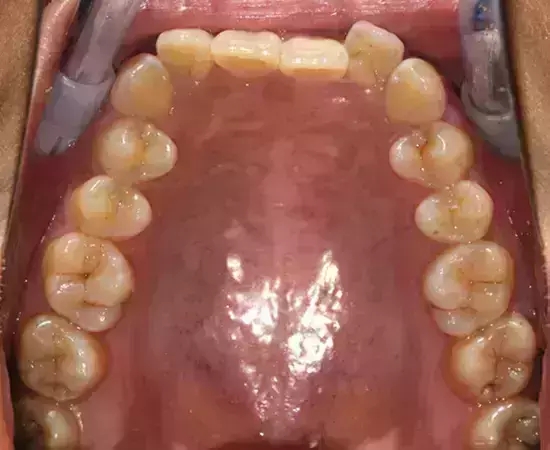

Damon 病例分享:安氏 II 類(lèi)二分類(lèi)露齦笑的矯治(董一磊)

治療前后對(duì)比